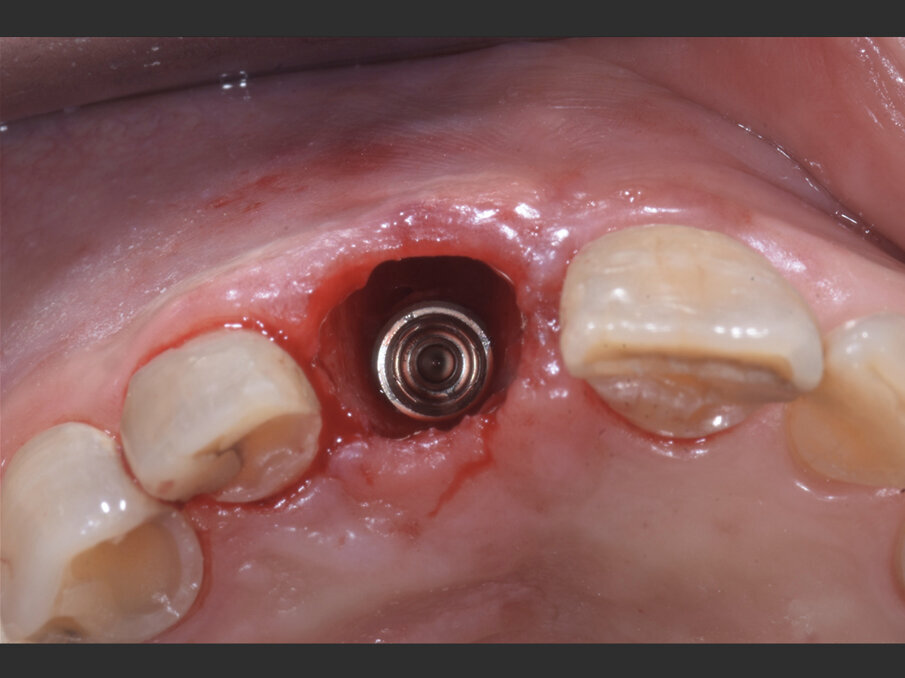

Il giorno dell’intervento, dopo somministrazione locale di articaina al 4% e adrenalina 1:100.000, l’elemento viene lussato delicatamente mantenendo integri i tessuti molli tramite l’uso di periotomi dedicati (Carda #2 e Carda #3 - Omnia) ed estratto. L’alveolo viene curettato e deterso con soluzione salina, e il tessuto epiteliale sulculare viene rimosso con una lama 15c, così da esporre il sottostante tessuto connettivale. Viene preparata un’osteotomia calibrata con frese dedicate, così da ingaggiare l’apice implantare (BLT Bone Level Tapered Roxolid SLActive, Straumann 4.1x14 mm) nel triangolo osseo apicale e palatale all’apice alveolare e posizionare il profilo coronale dell’impianto 1 mm al di sotto del margine della cresta vestibolare. Dopo il posizionamento implantare, con l’ausilio di un compattatore d’osso conico (Carda #4 - Omnia), il gap residuo vestibolare viene colmato con osso bovino deproteinizzato (Geistlich Bio-oss Collagen 50 mg, Geistlich) così da assicurare un perfetto riempimento tridimensionale dell’alveolo residuo. L’impianto viene infine posizionato con un torque di 50 N/cm (Figg. 3, 4a, 4b).

Fig. 4a - Impianto inserito lontano dalla corticale ossea vestibolare in modo da creare un gap superiore a 2 mm.

Fig. 4b - Il jumping space tra impianto e corticale ossee viene colmato con Geistlich BioOss Collagen.